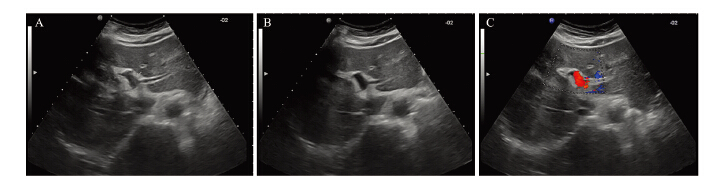

所有患者均按治疗计划顺利完成治疗。通过 超声和增强CT,观察瘤栓的分布范围、大小和 门静脉血流的变化。A组的近期有效率70.59% (24/34),B组的近期有效率67.74%(21/31), 两组疗效比较差异没有统计学意义(χ2=0.062, P=0.804),见表 2、图 2~3。

|

| A: left branch of PVTT before 3-DCRT; B: the tumor thrombosis disappeared after 3-DCRT; C: color Doppler rheography after 3-DCRT 图 3 Ⅰ级癌栓三维适形放疗前后声像图 Figure 3 Contrast image of grade Ⅰ PVTT before and after 3-DCRT 表 3 |